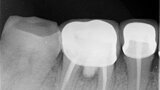

Fig.1b: Pre-op radiograph taken by the author in relation to tooth #46 (January 2019).